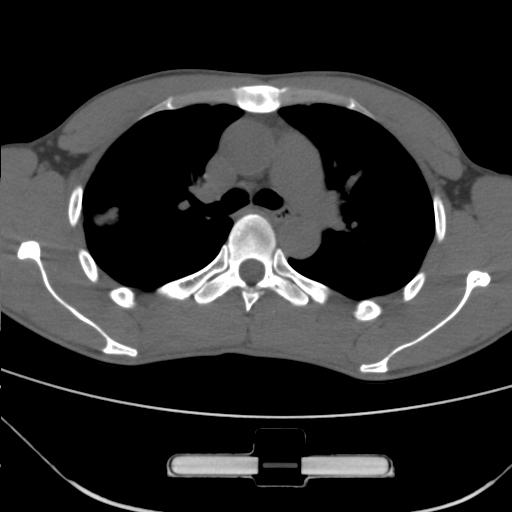

车祸伤者

右肺上叶后段近胸膜下结节样异常密度灶,似见分页及毛刺,考虑右肺上叶周围型肺ca,建议穿刺病理检查

周围型肺ca与炎性假瘤待鉴别。建议穿刺病理检查

考虑周围型肺癌

考虑周围型肺癌可能性大,建议穿刺病理检查

缺乏病史,症状体征,但这个孤立结节具备了几乎所有的恶性征象:分叶,毛刺,空泡征,胸膜凹陷征,血管集束。

考虑右肺上叶后段周围型肺癌。